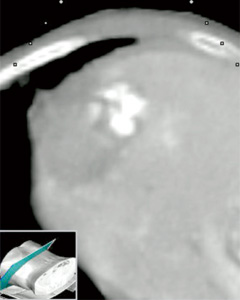

■ コントラスト対応探触子(図6)

コントラスト対応の探触子には,標準腹部コンベックス“EUP-C715,C514”以外に穿刺専用探触子“EUP-B514”,穿刺専用マイクロコンベックス“EUP-B512”があり,診断だけではなく,造影超音波のRFA治療への応用にも対応している。

図6 コントラスト対応穿刺プローブの例

a:腹部穿刺用コンベックス “EUP-B514”

b:腹部穿刺用マイクロコンベックス“EUP-B512”